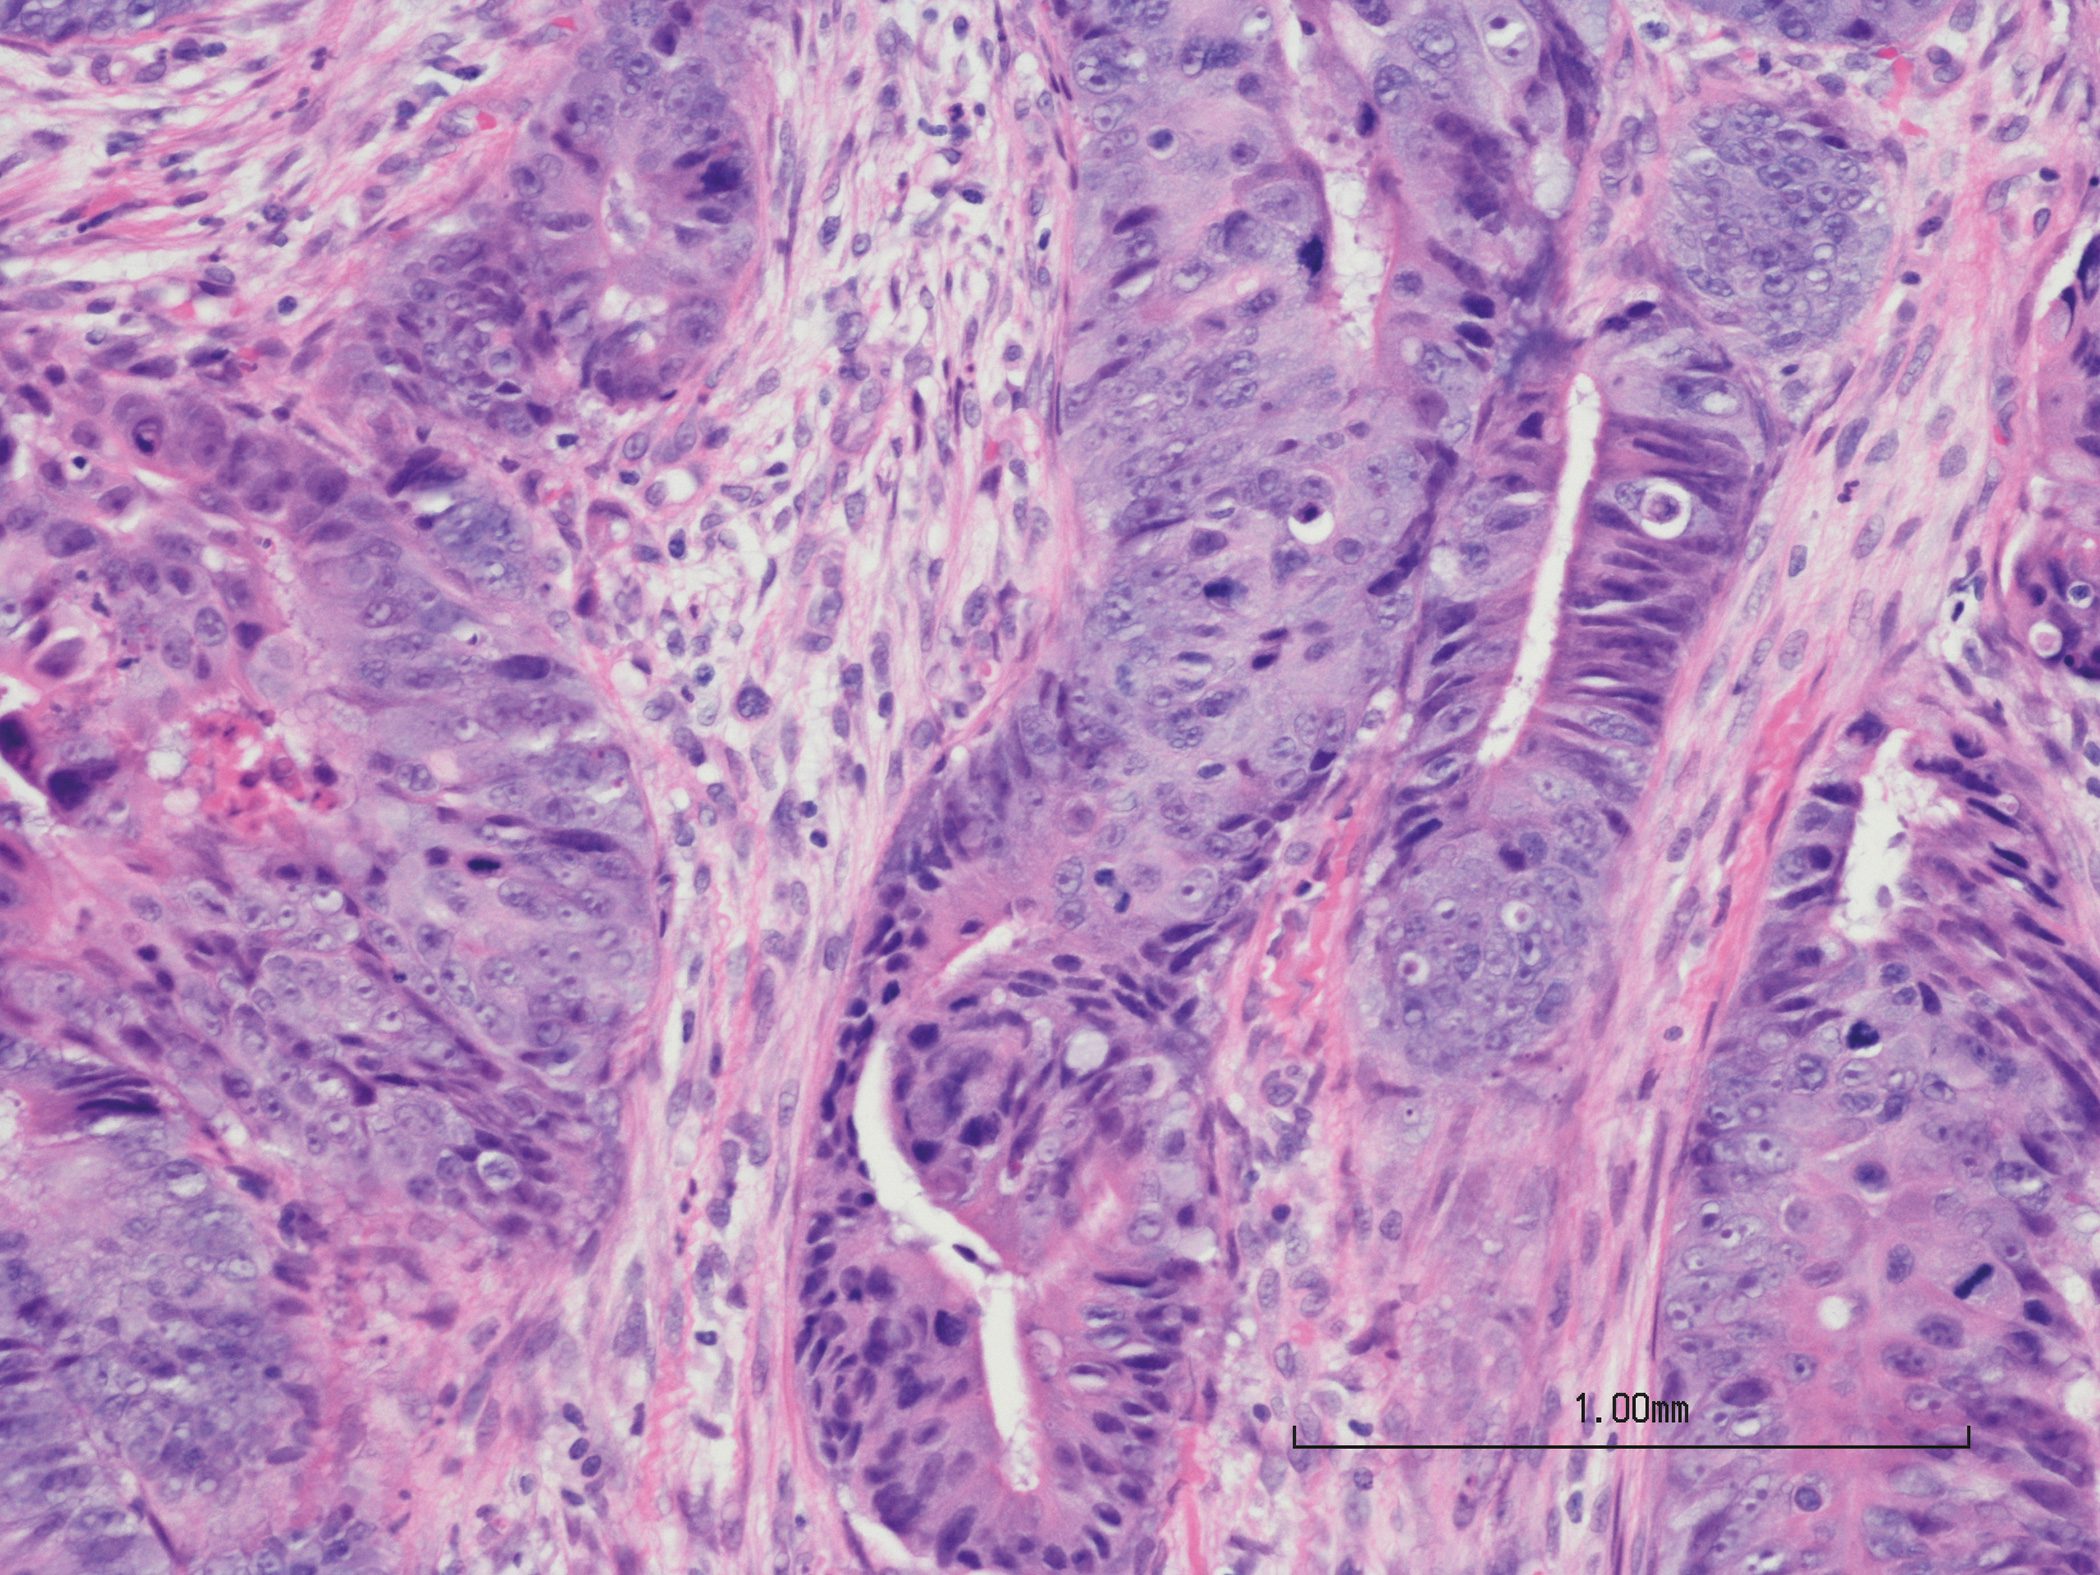

Anhand des Fallbeispiels einer 85-jährigen Patientin mit einem CVI-dominierten «Ulcus cruris mixtum» veranschaulichten Prof. Dr. Sebastian Probst und Prof. Dr. Ewa-Klara Stürmer die Problematik chronisch-stagnierender Wundheilung und zeigten auf, wie es bei dieser Patientin gelungen ist, durch Interventionen mit einem Fokus auf Infektions- und Exsudatmanagement den Wundheilungsprozess anzustossen.